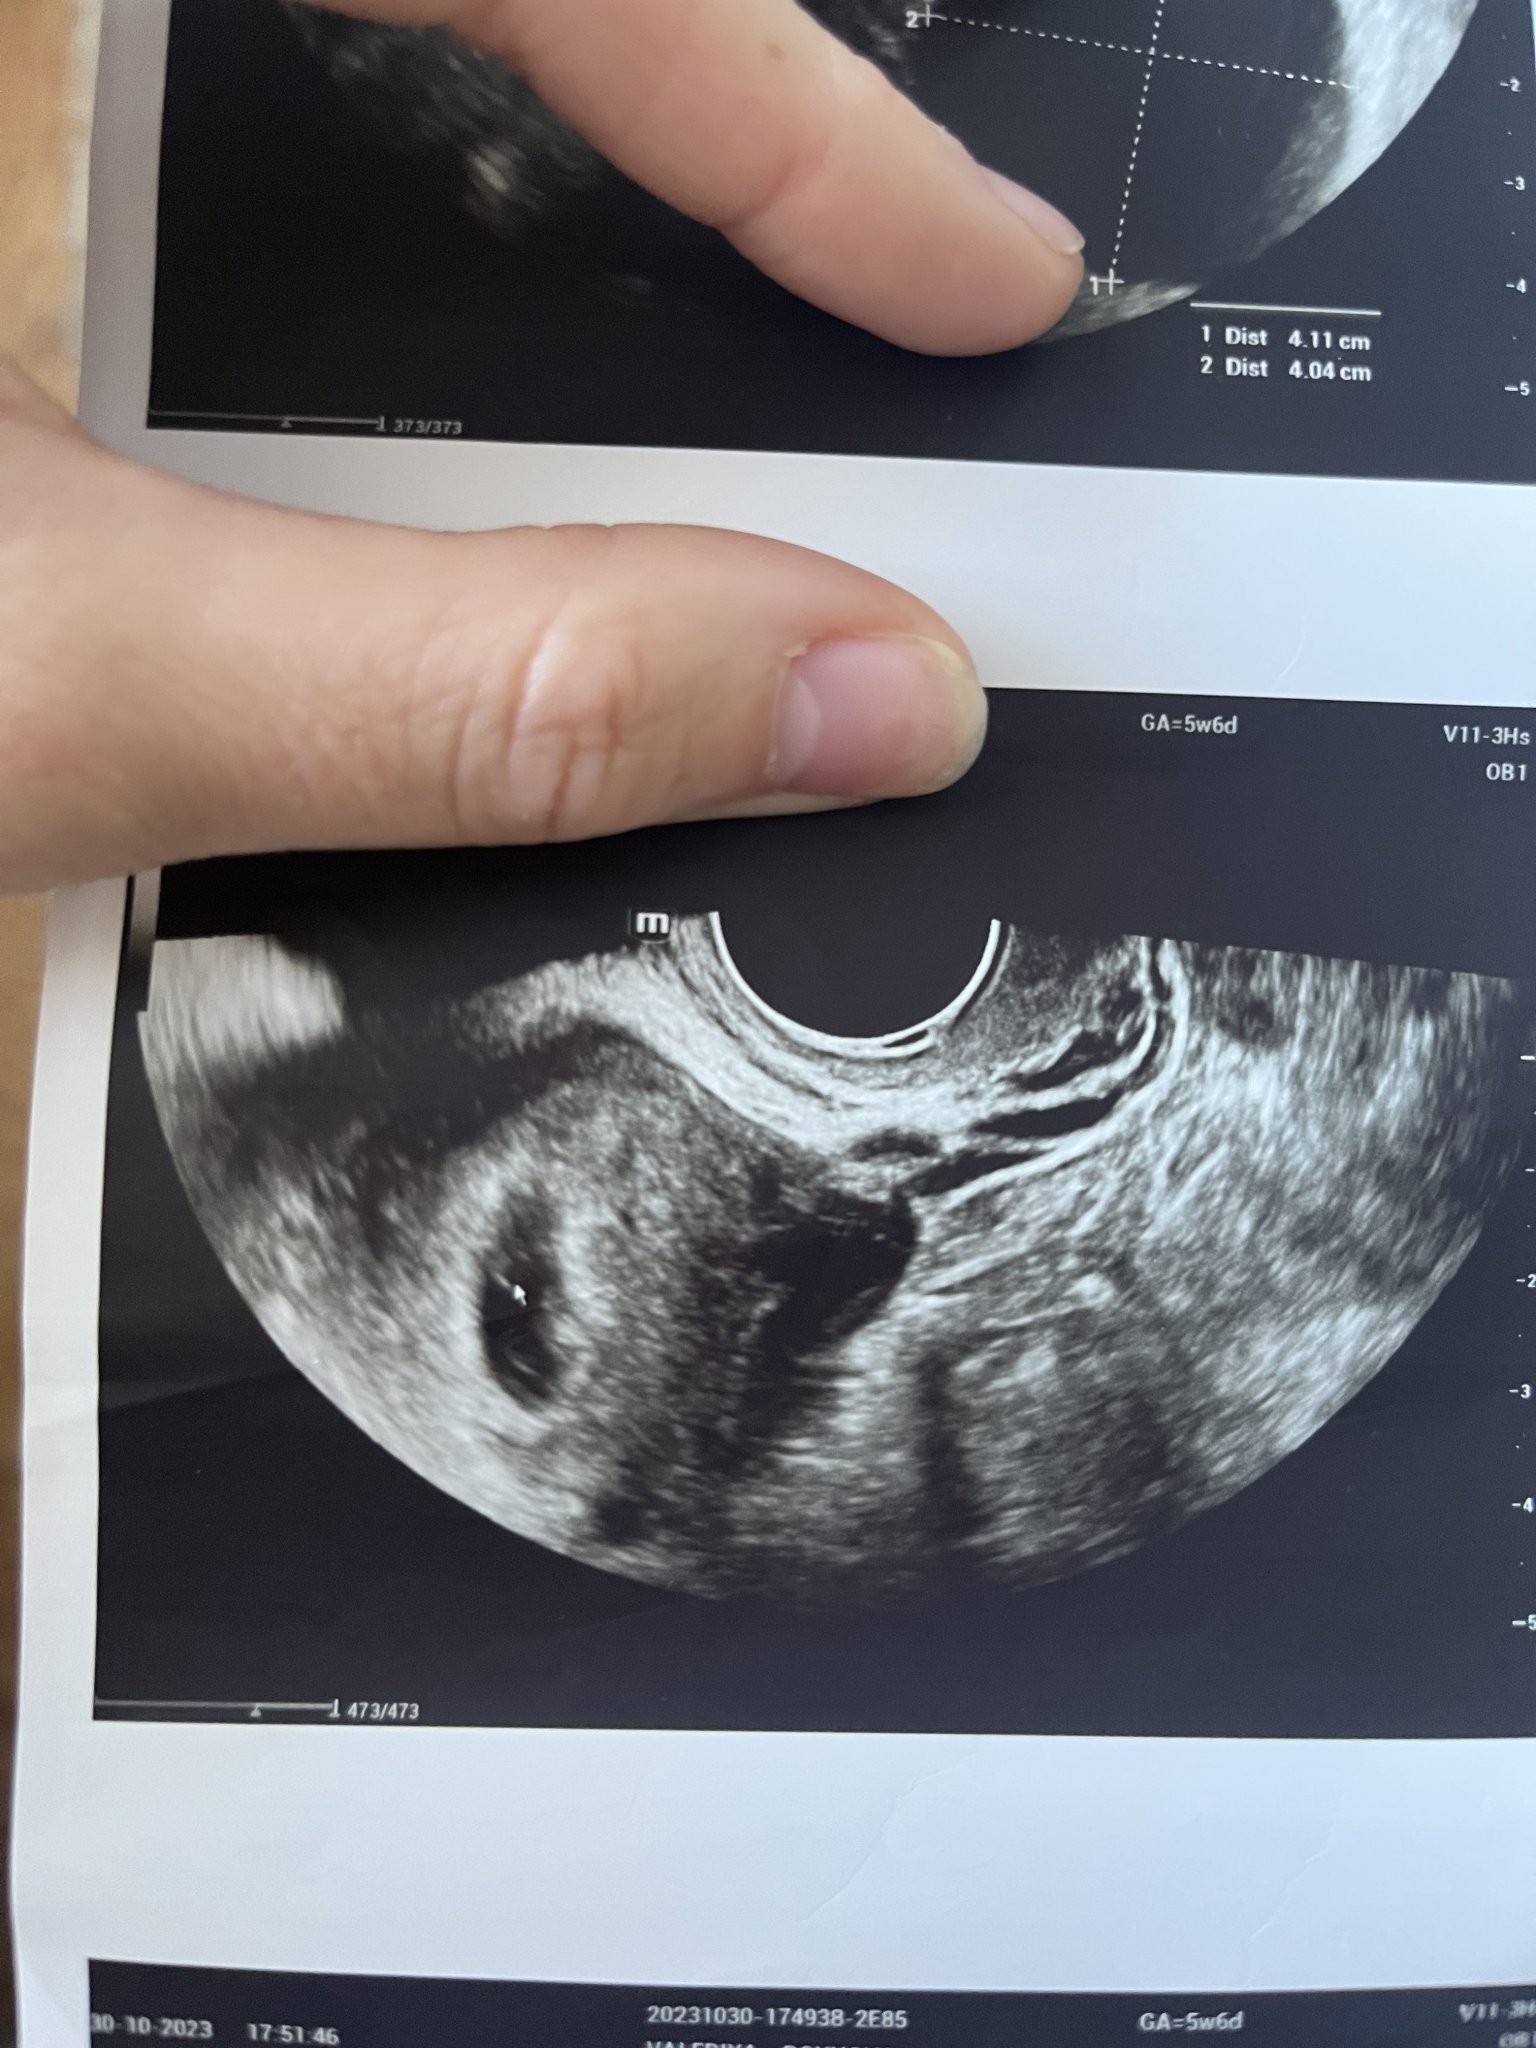

• Мнения: 16

Здравейте ! Първият ми ден от последната ми менструация беше на 20.09 ( като имам нередовен цикъл ).След няколко положителни теста , днес беше и първият ми преглед . Ще прикача снимки от него . Според лекаря съм имала късна овулация и съм още в самото начало на бременноста . Видя се правилно закрепено плодно сакче , с големина 4мм ( около 5 и 6 г.с), но без ембрион , защото е още много рано . След 2 седмици пак съм на преглед . Притеснява ме големината на плодния сак , не е ли малък ?